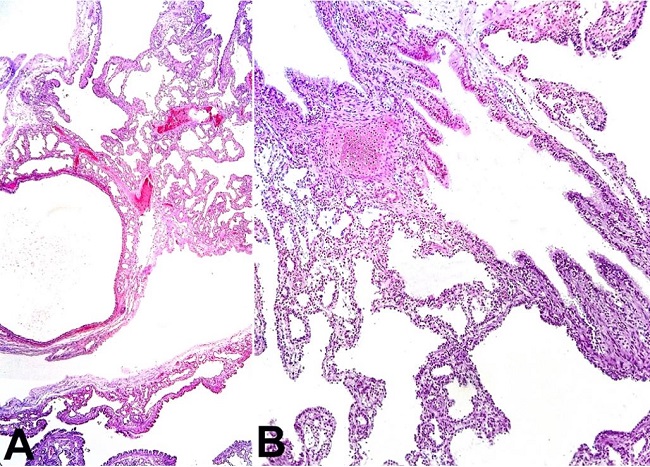

The thoracic organs were fixed in formalin for subsequent dissection ( Figure 2A ). The right lung cut surface showed to be markedly altered by the presence of numerous contiguous cystic formations outlined by thin walls, imparting a honeycomb appearance. It additionally showed two lobes, both affected by the malformation. The left lung had two lobes and appeared compact ( Figure 2B ).